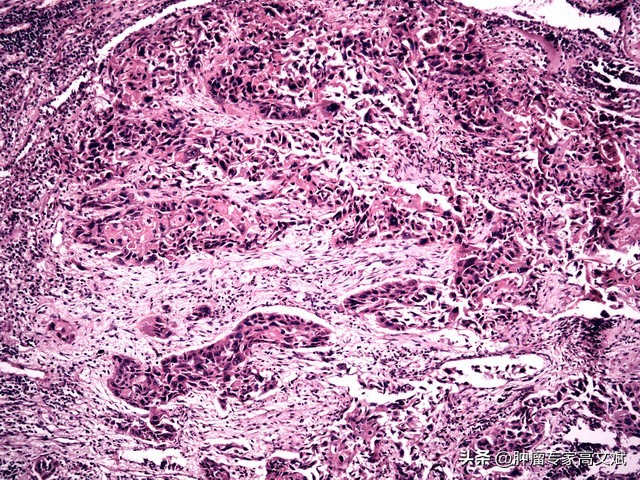

大家都知道,双肺是人体重要的呼吸器官,平静、顺畅的一吸一呼可以保证人体正常呼吸功能的完成。但是,当肺部发生疾病的时候,这种平静的状态就会被打破。当我们需要再进一步了解肺内疾病的具体原因或者情况的时候,除了拍摄各种影像学检查以外,如果能从肺部病变的地方取出一些病变的组织进行化验、病理检查就显得尤为重要了,这也就是我们常说的肺部活检技术。在目前的临床诊疗中,肺部活检技术对于肺部占位性疾病的诊断、治疗具有着尤其重要的地位,也是明确诊断,为进一步治疗提供依据的主要诊查手段之一。

虽然经皮肺穿刺活检术在诊疗中具有一定的危险性,合并有一些并发症,但是其安全性还是毋庸置疑的的,经过多年的摸索,此项技术已经达到了相当成熟的地步,其主要适用于在肺内发现了孤立的或者多发性的肺结节,需要确定其良恶性,或者具体的组织学类型的。临床上已经发现了肺部转移病灶,但是还需要明确具体的组织学类型,或者为寻找原发灶提供诊断依据的。在临床上虽然已经实施了痰细胞学、支气管镜检查,但是未能确诊肺部疾病的具体诊断的。肺部恶性肿瘤放疗、化疗前需明确组织类型、基因类型,以便制定治疗方案的。部分肺部良性疾病需要进一步确诊的。对于部分肺内发生实变的患者,需要实施微生物学标本检查的,也可以实施肺穿刺活检的方法进行标本的取材。